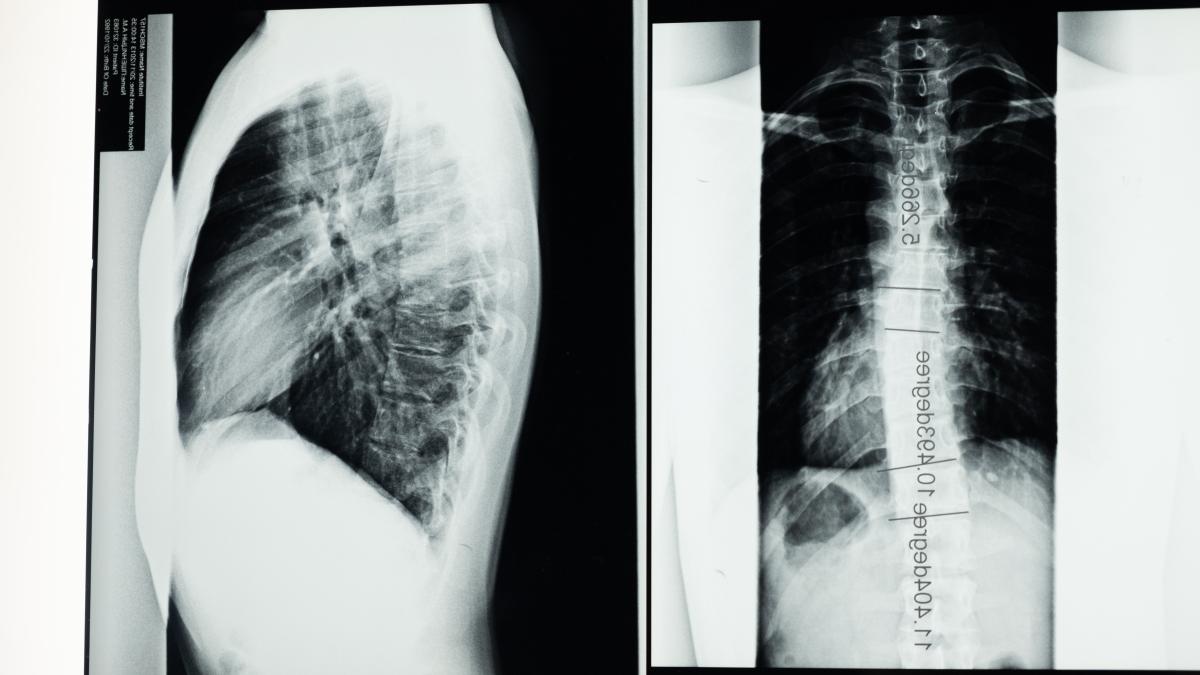

Scolioza la copii: exerciții și tratamente

Scolioza este o tulburare în alinierea coloanei vertebrale. Această deformare este frecventă la copiii în creștere. Din fericire, activitatea fizică promovează flexibilitatea spatelui, ameliorând astfel simptome precum durerea. Iată câteva exerciții și întinderi de făcut pentru copiii cu scolioză.

Există multe motive care pot face ca alinierea coloanei vertebrale să nu se alinieze. Printre acestea se numără și factori dobândiți din traume sau ca urmare a unei alte boli. De asemenea, există cauze congenitale, adică de la naștere. Prin urmare, este important să se diferențieze o scolioză structurală de una funcțională.

În funcție de severitatea deformării, tratamentele variază de la un plan de exerciții adaptat la proceduri chirurgicale. În cazurile mai ușoare de înclinare a coloanei vertebrale, kinetoterapeutul va proiecta un program cu activități pentru a flexa , întări și prelungi fiecare zonă a spatelui.